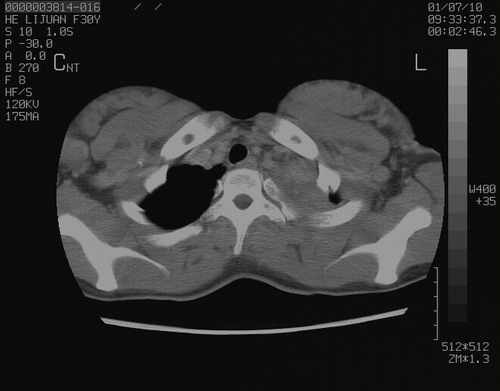

怀孕3个月时(2009-3至4月间),自述突感左侧前后胸疼痛1天,以前胸明显,随后偶感闷痛,余未见异

左肺尖脊柱旁沟肿块,境界清楚,边缘光滑,密度不均,内有多发点片状钙化,考虑良性肿瘤,骨软骨瘤或神经源性肿瘤可能,肺错构瘤不除外。

左后上纵隔见一类圆形肿块影,外侧边界清,密度不均匀,内可见点状钙化影,增强呈不均匀强化,考虑神经源性肿瘤可能。期待病理结果。